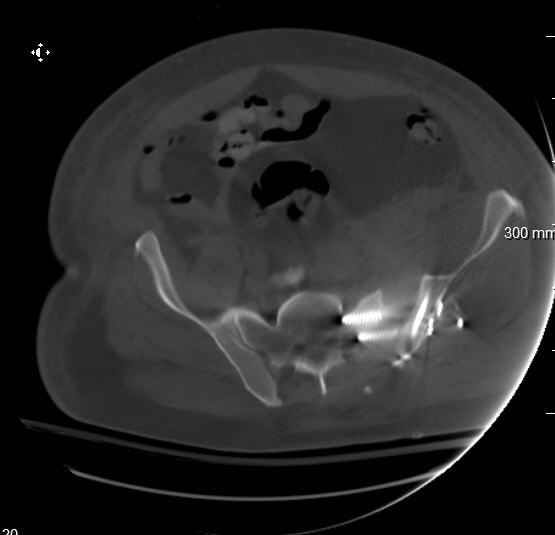

Re: APC III pelvis fx

My plan to revise fixation is in line with your suggestion - plate symphysis and anterior approach to SI joint. It appears from post - failure CT scan that the path of the more cephalad IS screw may be helpful to place a longer screw to engage opposite illiac wing as an option, or just anterior SI plates. not likely to do this tomorrow as he remains in a fragile clinical situation regarding his pulmonary status, and profound edema/induration around his pelvis/abdomen and thighs.